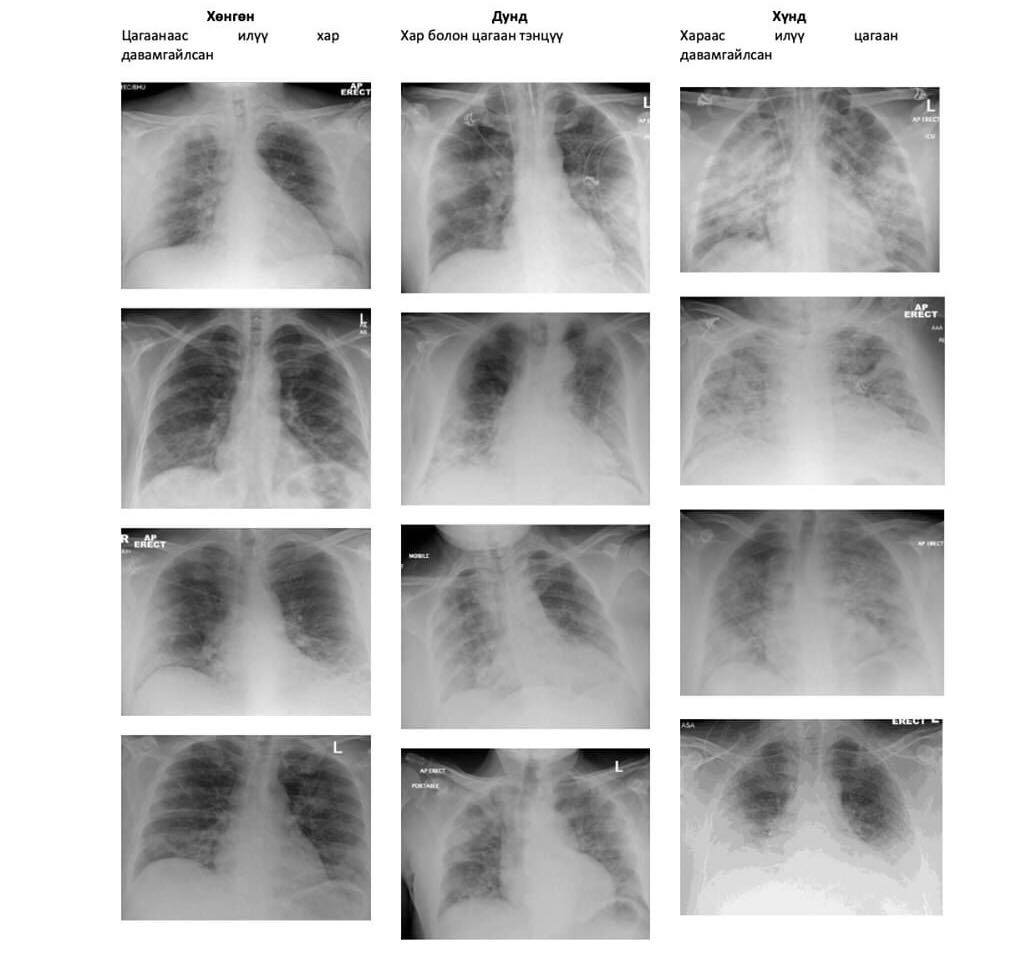

Дараах зурагт корона вирусээр хөнгөн болон дунд, хүндээр өвчилсөн иргэдийн уушигны рентген зурагны харьцуулсан харьцуулалтыг хүргэж байна.

Тус зургаас харахад хар харагдаж байгаа нь эрүүл харин цагаарч харагдаж байгаа нь уушги гэмтсэн байгааг харж болох юм.